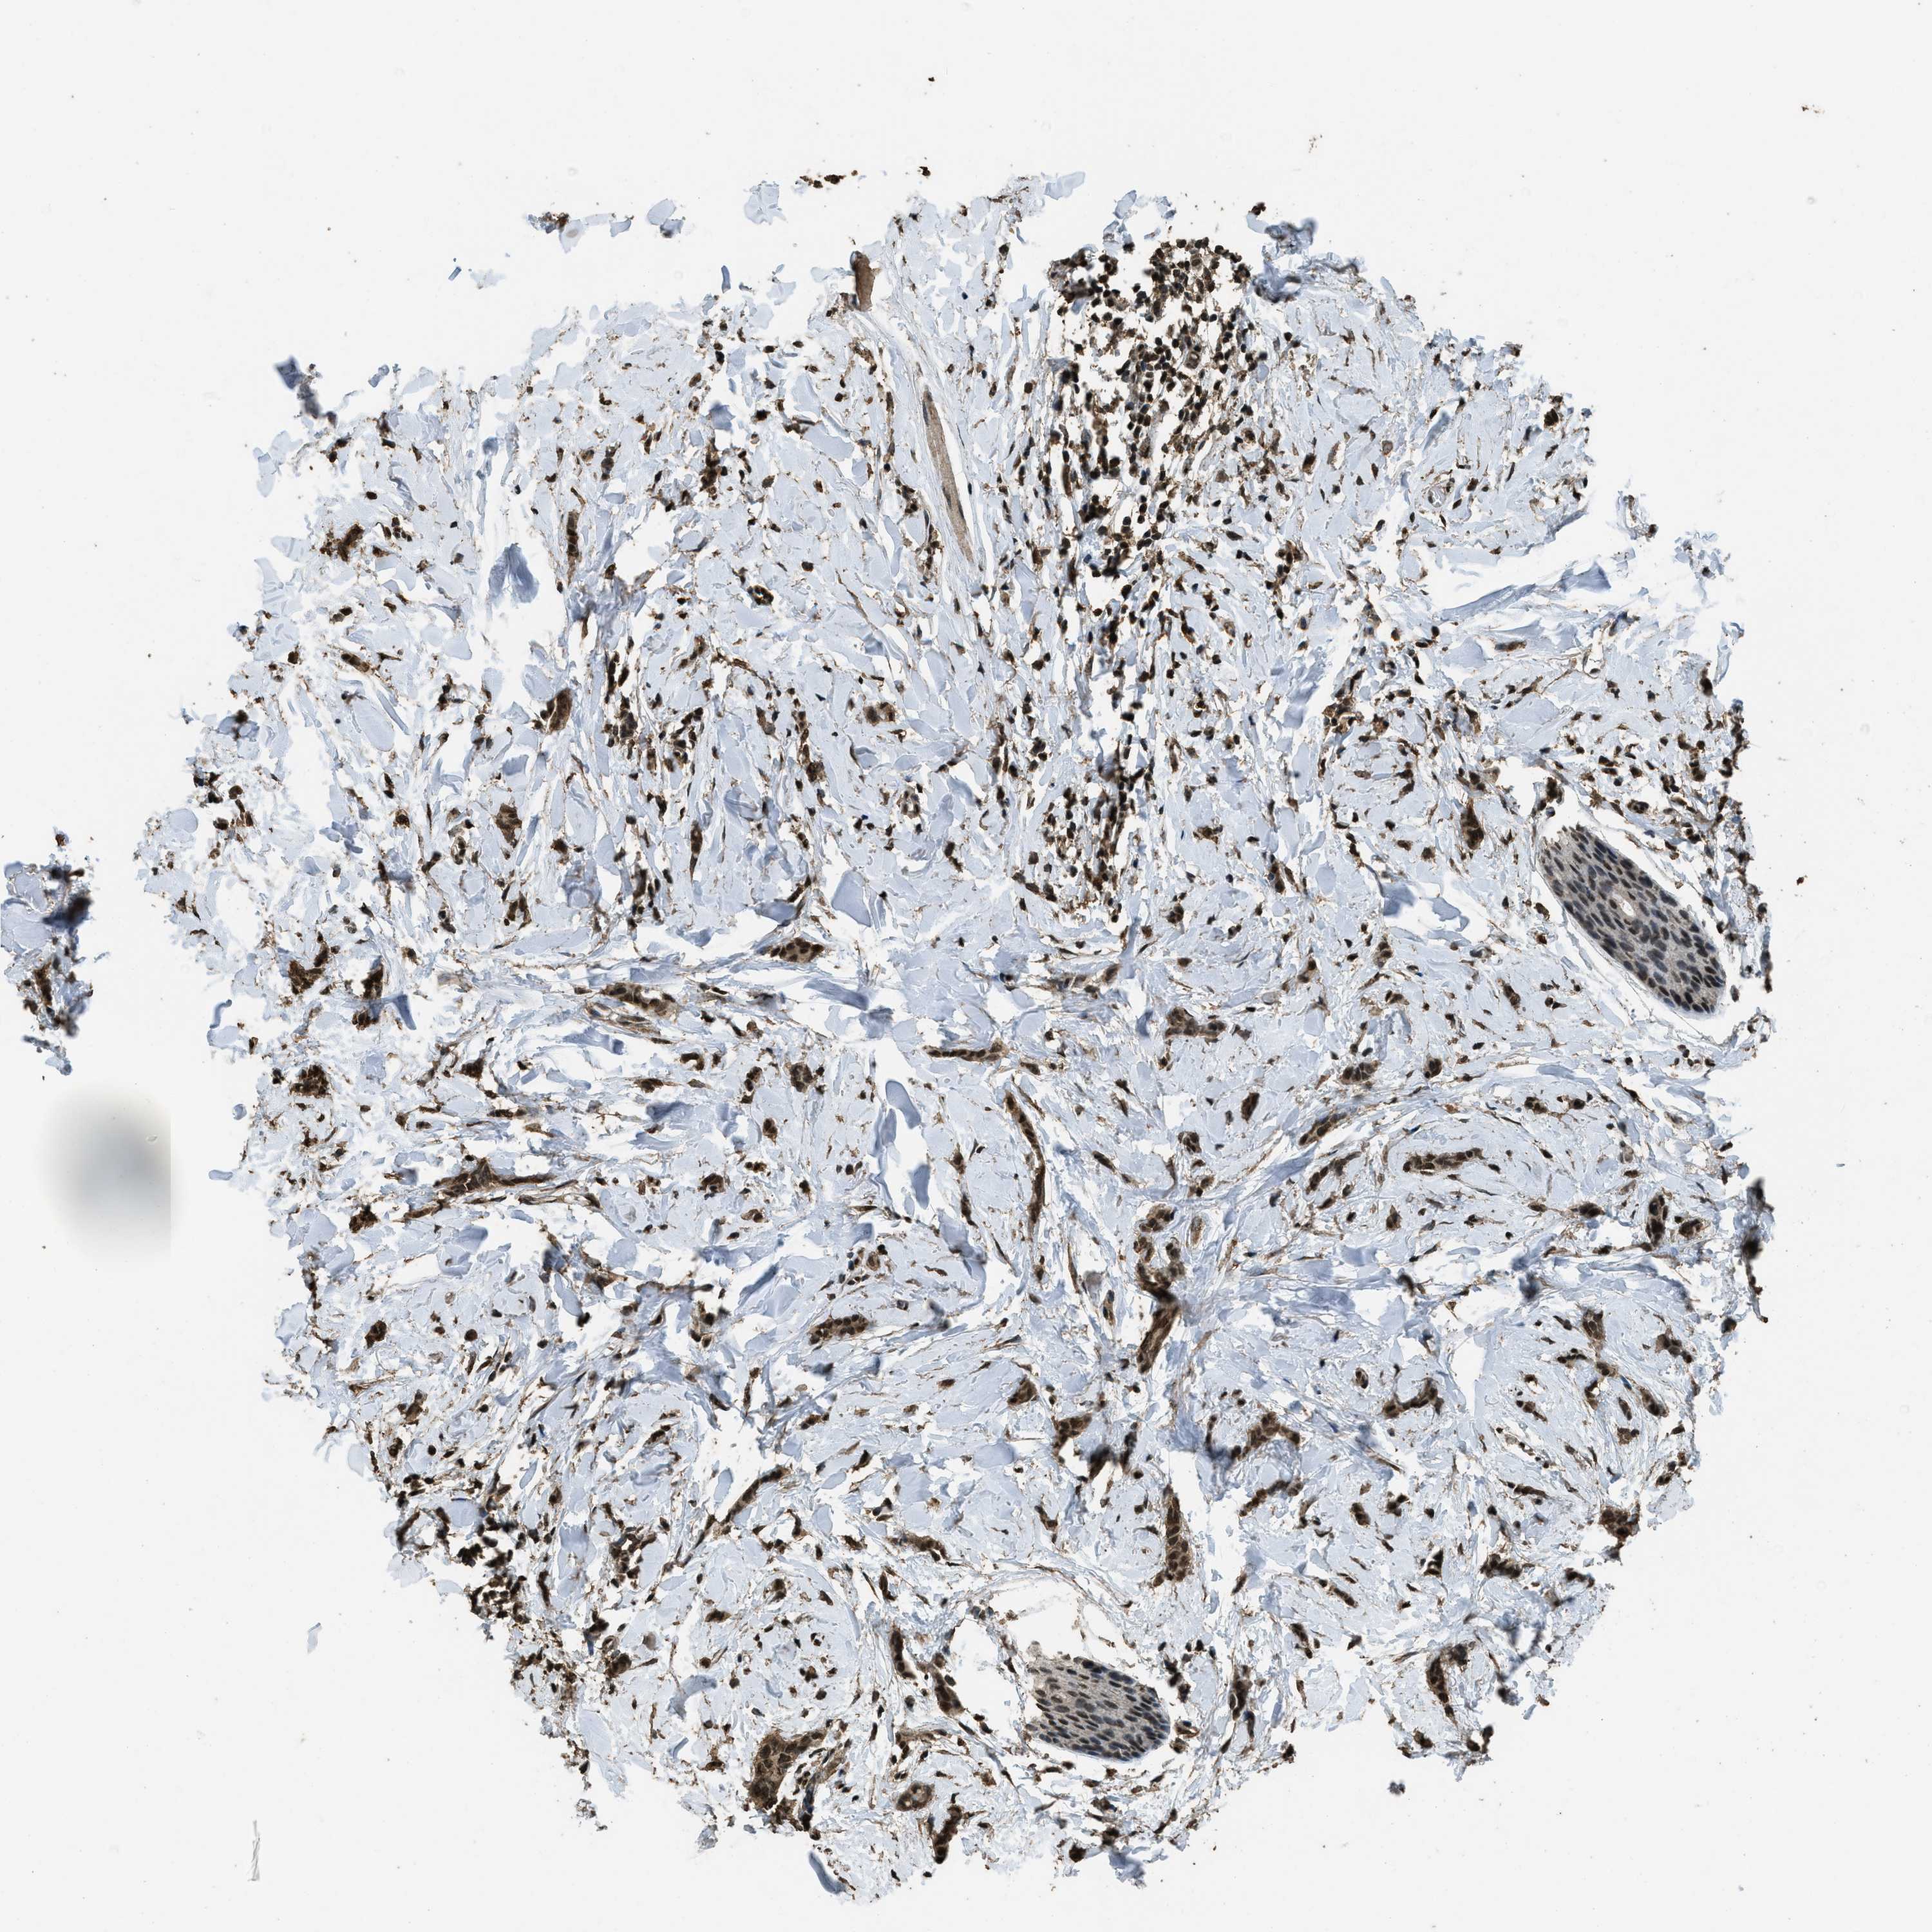

CANCER BREAST CANCER Show tissue menu

BRCA TCGA BRCA VALIDATION PROTEIN EXPRESSION